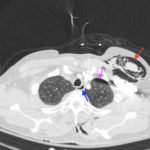

Plain film anteroposterior (AP) radiography of the chest shows left-sided subcutaneous emphysema (red arrow) with overlapping muscle striations of the pectoralis major (green arrow). After chest tube placement (blue arrow), AP chest radiography shows persistent left-sided subcutaneous emphysema (red arrow). CT of the chest shows pneumomediastinum (blue arrow), left apical pneumothorax (pink arrow), and subcutaneous emphysema (red arrow) at the level of T2. At the level of T6, rib fractures can be visualized on the CT (yellow arrow). At the level of T8, left sided pneumothorax is also seen (pink arrow) as the absence of lung tissue on CT.

In this patient, given the findings of multiple bilateral rib fractures, bilateral hemothorax/pneumothorax and multiple spine fractures, bilateral chest tubes were placed which had immediate output. The patient was admitted to surgical intensive care unit for chest tube management, pulmonary hygiene and further management of his other injuries.